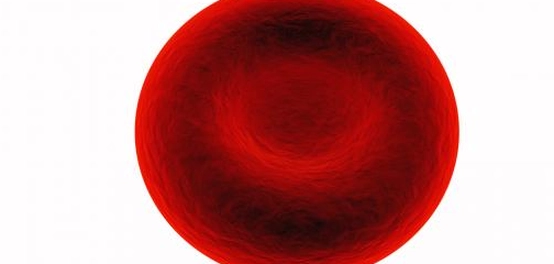

فقر الدم، أو الأنيميا (Anemia)، هو حالة طبية تتسم بنقص في عدد خلايا الدم الحمراء أو انخفاض في مستوى الهيموغلوبين في الدم. الهيموغلوبين هو البروتين الموجود في خلايا الدم الحمراء الذي يحمل الأكسجين إلى جميع أنحاء الجسم. يمكن أن يحدث فقر الدم نتيجة لعدة عوامل، بما في ذلك نقص إنتاج خلايا الدم الحمراء، أو فقدان الدم بشكل سريع نتيجة النزيف، أو تدمير خلايا الدم الحمراء بشكل مفرط. كذلك، يمكن أن يؤدي نقص بعض العناصر الغذائية الأساسية لإنتاج خلايا الدم الحمراء، مثل الحديد والفيتامينات، إلى ضعف في إنتاج هذه الخلايا والإصابة بفقر الدم. في هذه الحالات، لا يوجد ما يسمى بحامل فقر الدم، بل تكون الإصابة ناتجة عن أسباب خارجية قابلة للعلاج بزوال السبب.

في المقابل، هناك أنواع أخرى من فقر الدم تنجم عن اضطرابات جينية، مثل فقر الدم المنجلي (Sickle cell disease) والثلاسيميا (Thalassaemia). هذه الأمراض ناتجة عن خلل في الجينات المسؤولة عن إنتاج الهيموغلوبين، مما يؤدي إلى تشوه في شكل خلايا الدم الحمراء أو ضعف قدرتها على حمل الأكسجين.

في سياق أمراض فقر الدم الوراثية، مثل الثلاسيميا وفقر الدم المنجلي، قد يحمل الشخص نسخة واحدة فقط من الجين المتسبب في المرض، والتي ورثها من أحد الوالدين. في هذه الحالة، قد لا تظهر على الشخص أي أعراض واضحة لفقر الدم، أو قد تظهر أعراض خفيفة جدًا في بعض الحالات الخاصة. يعود ذلك إلى وجود جين سليم آخر يعمل على إنتاج كميات كافية من الهيموغلوبين الطبيعي في الدم. يُطلق على الشخص في هذه الحالة اسم “حامل فقر الدم”.

كما ذكرنا سابقًا، قد تنجم الإصابة بفقر الدم عن أسباب متنوعة. ولكن في حال كان السبب وراثيًا، كما هو الحال في فقر الدم المنجلي، فإن الإصابة تحدث عندما يمتلك الشخص نسختين من الجينات المسؤولة عن المرض، أي أنه ورث الجين المعيب من كلا الوالدين. هذا يؤدي إلى انخفاض عدد خلايا الدم الحمراء السليمة عن المعدل الطبيعي، وبالتالي ظهور أعراض فقر الدم على الشخص المصاب.